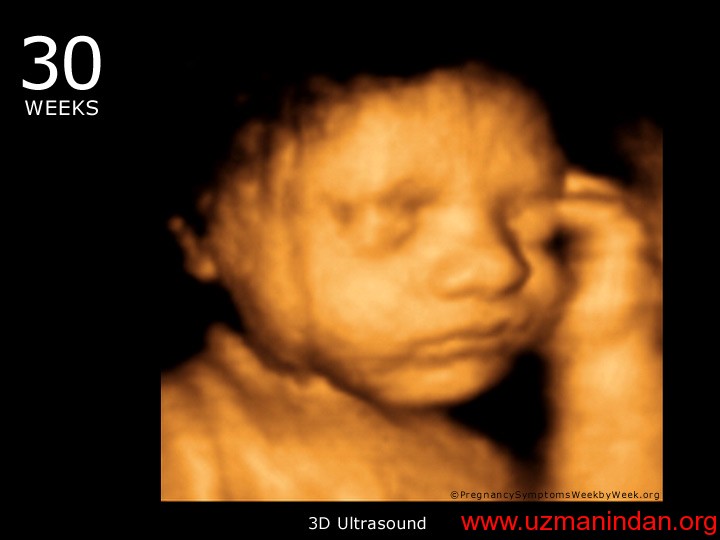

28 – 30 haftalık fetus

30 haftalık bebek görünümü anne karnında.jpg